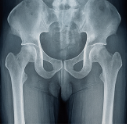

초기에는 무증상이 많지만, 진행되면 골반·허리·엉덩이가 둔하게 아프고 오래 앉기 힘들 수 있습니다. 전립선암 초기증상 단계라면 미세하거나 간헐적일 수 있어, ‘평소와 다른 통증’에 주의를 기울이세요.

배뇨곤란·야간뇨·잔뇨감은 비대증과 매우 유사합니다. 전립선암 초기증상과 비대증은 검사로만 구분되므로, 임의로 결론 내리지 말고 병원에서 영상·혈액·조직 검사를 통해 확정해야 합니다.